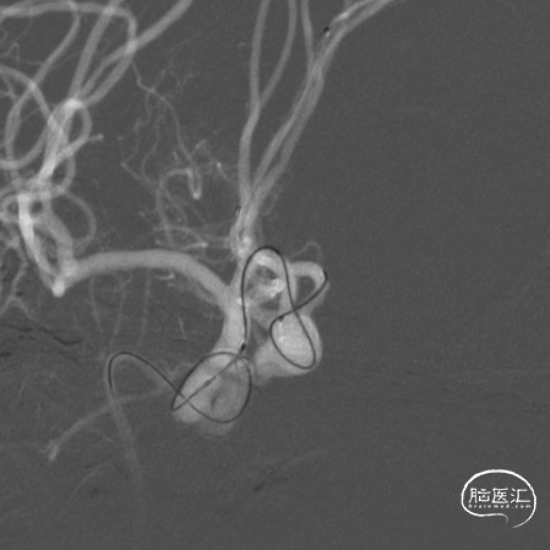

置入第一枚Atlas支架 3mm×15mm。

置入第二枚Atlas支架 4mm×21mm。

造影示“T”型支架左侧Atlas支架 3mm*15mm 、右侧 Atlas支架 4mm*21mm,动脉瘤致密栓塞,不显影。双侧A2段显影良好。

Atlas支架是激光雕刻开环支架,在不同直径动脉内释放时,短缩及延长非常微小。可以在释放之前,准确预估其完全放开后尾端的位置,支架组合能否形成完美“T”型,完全覆盖动脉瘤颈部非常重要。

在做“T”型支架时,两条支架释放的先后顺序各有千秋。本病例是先释放“竖”后“横”,这样可以是使“竖”支架尾端不受干扰地充分张开,“横”支架和前者充分贴合。